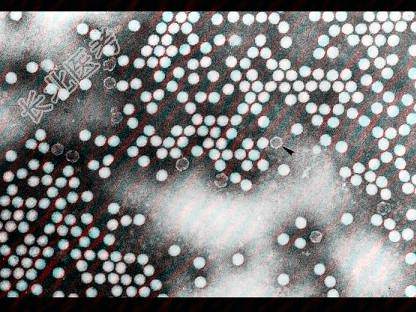

- 多项选择题关于图中所示的脊髓灰质炎病毒,无误的是 ( )

A、对热、干燥及氧化消毒剂敏感

B、在大便、污水中仅可存活1~2个月

C、能抵抗乙醚、乙醇和胆盐,在pH值3.0~10环境中活力稳定

D、有3型病毒,世界各地流行以Ⅰ型居多

E、脊髓灰质炎病毒是单股RNA,直径16 nm